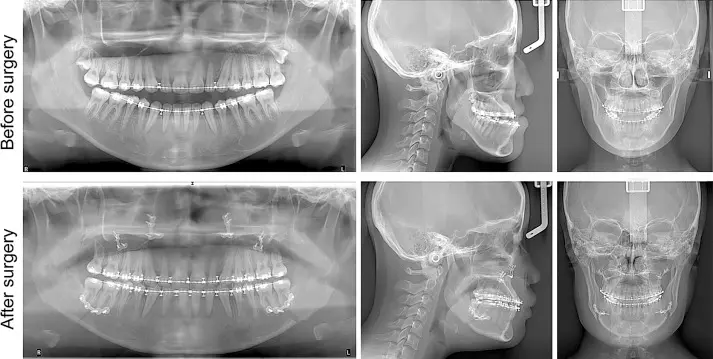

ارتوسرجی یا ارتودنسی همراه با جراحی فک یک روش درمانی است که برای اصلاح مشکلات فکی و دندانی جدی مورد استفاده قرار میگیرد. در این روش، ابتدا ارتودنسی برای تنظیم دندانها و آمادهسازی آنها انجام میشود، سپس جراحی فک برای اصلاح ساختار فک و بهبود عملکرد آن صورت میگیرد. این درمان میتواند مشکلاتی مانند فک جلو، فک عقب، عدم تقارن صورت، بروکسیسم و مشکلات تنفسی را اصلاح کند.

برخی از ناهنجاریهای فکی و دندانی تنها با ارتودنسی قابل اصلاح نیستند و نیاز به ترکیب آن با جراحی فک دارند. این روش که به ارتوسرجری معروف است، برای بیمارانی که مشکلات شدیدی در موقعیت فکها دارند، توصیه میشود. ارتودنسی قبل از جراحی، دندانها را در موقعیت مناسب قرار میدهد و پس از جراحی، تنظیمات نهایی انجام میشود تا فک و دندانها هماهنگ شوند.

۲. ارتودنسی پیش از جراحی: دندانها با براکتهای ثابت مرتب میشوند تا برای جراحی آماده شوند.

3. جراحی فک: جراح فک و صورت موقعیت استخوان فک را اصلاح میکند تا هماهنگی بهتری ایجاد شود.

4. ارتودنسی بعد از جراحی: برای تکمیل درمان و تثبیت نتایج، تنظیمات نهایی دندانها انجام میشود.